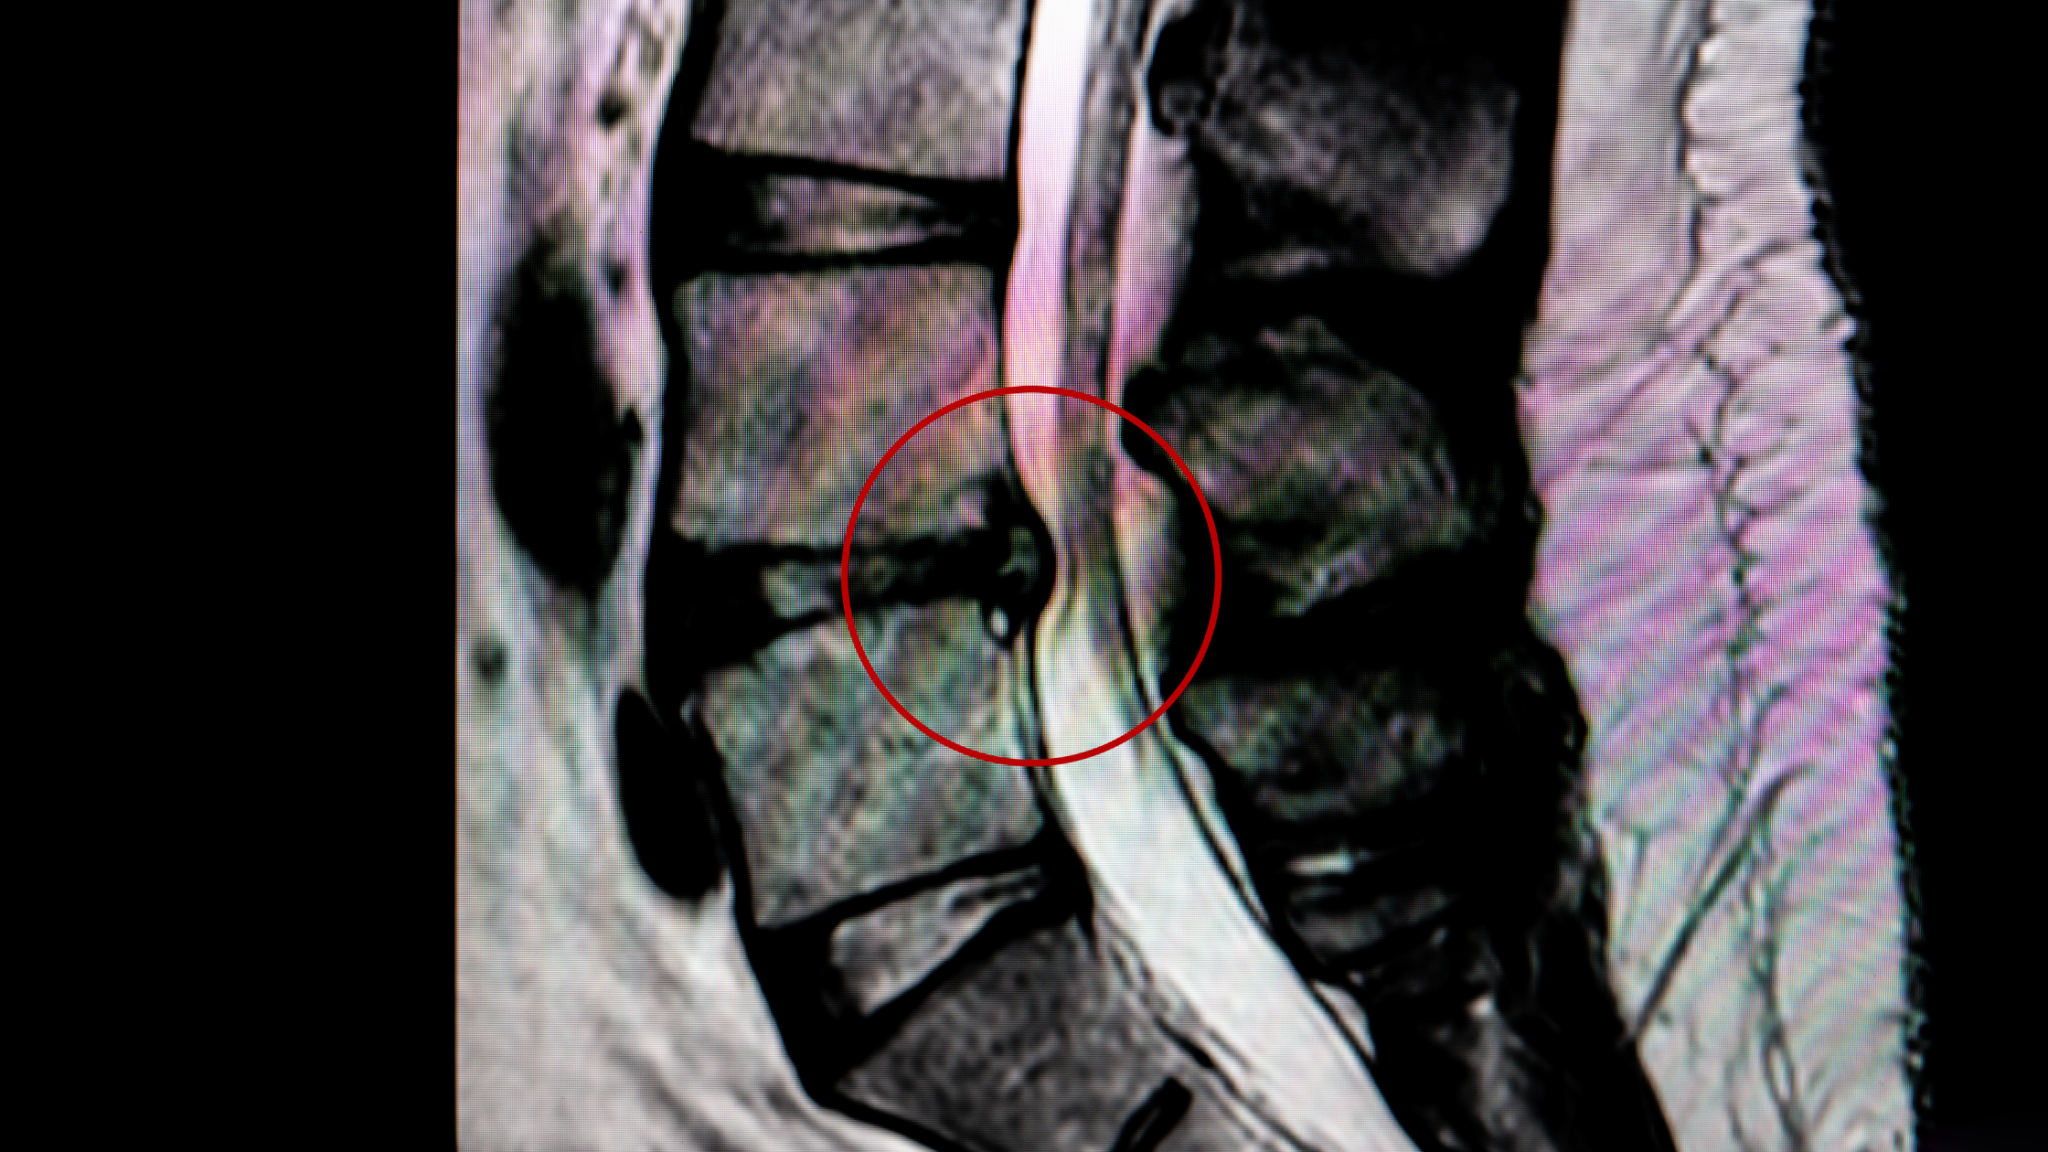

Грыжа давит на нерв

Грыжа давит на нерв 115 фото